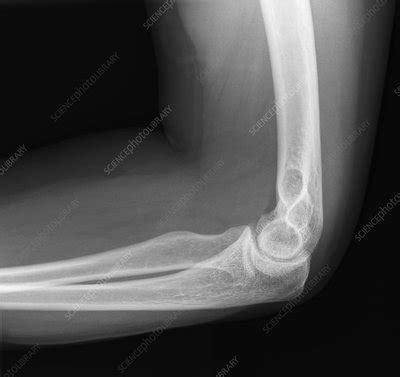

Elbow X Ray Image - The humerus projects over the olecranon. Web the elbow series is a set of radiographs taken to investigate elbow joint pathology, often in the context of trauma. Use common lines which are helpful in interpreting the image. Web normal anatomy on a lateral elbow image. Soft tissue areas, cortical margins, trabecular.